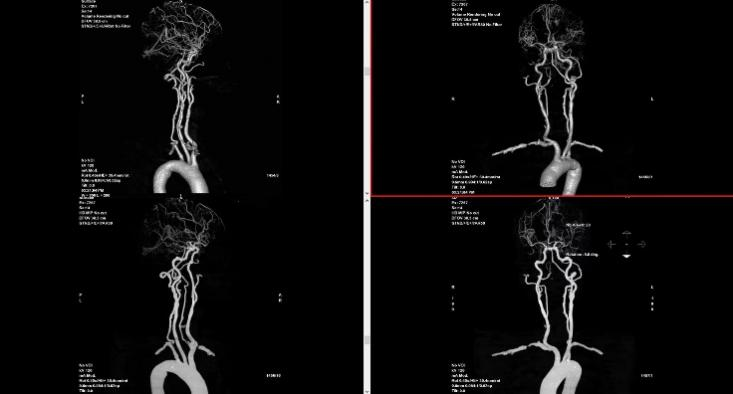

我们的服务项目涵盖了全身各部位的影像检查,包括但不限于:头部、颈部、胸部、腹部、盆腔、四肢等部位的CT、MRI、DR等检查。我们还提供特殊的影像检查服务,如血管造影、MR多功能成像等。例如:

血管造影: